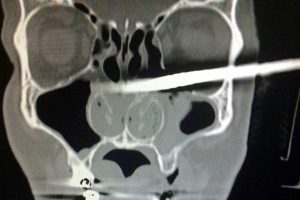

40-летний Камил Подвинский (Kamil Podwinski) пострадал во время ремонта, который он делал в собственном доме. Согласно изданию трудолюбивый мужчина поскользнулся и неудачно упал, напоровшись головой на рейку, которую он хотел было прибить. Палка прошла насквозь, пробив череп, по нижнему краю глазницы и вышла у затылка.

Но это не самое страшное для мужчины. Растерявшиеся врачи не сразу смогли сделать рентген пациенту, так что ему пришлось мучиться еще долгое время до прибытия команды пожарников, которые со всей аккуратностью укоротили брусок, торчавший в голове Подвинского.